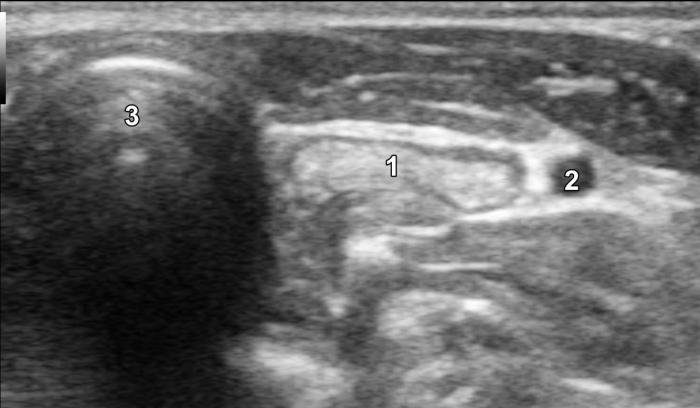

La glándula tiroides en perros y gatos está constituida por dos lóbulos situados a ambos lados de la tráquea cervical, con disposición longitudinal y una forma fusiforme o alargada que se extiende desde el cartílago cricoides hasta la entrada torácica superior2. En condiciones normales, cada lóbulo presenta contornos bien definidos, cápsula hiperecogénica delgada y parénquima homogéneo, con una ecogenicidad generalmente igual o ligeramente superior al músculo esternohioideo adyacente3,8. En la imagen transversal, los lóbulos suelen adoptar una configuración oval o ligeramente triangular (Figura 1); en longitudinal, se observa una forma alargada con extremos redondeados y orientación paralela a los vasos carotídeos y la tráquea1 (Figura 2).

La localización anatómica superficial de la glándula, junto con su estructura relativamente uniforme, facilita su identificación mediante ultrasonografía de alta resolución. Entre los reparos anatómicos más importantes para su localización se encuentran las arterias carótidas comunes (laterales), la tráquea (medial) y los músculos esternotiroideos (ventrales), mientras que el esófago puede constituir una referencia dorsal del lóbulo izquierdo15 (Figuras 3 y 4).

Las glándulas paratiroides, encargadas de la regulación del metabolismo del calcio, pueden ser evaluadas mediante ecografía, aunque su identificación depende de la experiencia del ecografista, la calidad del equipo y la presencia o no de patología subyacente3. En condiciones normales, estas glándulas son pequeñas (menores de 3-4 mm), isoecogénicas o ligeramente hipoecogénicas respecto al tejido tiroideo (Figura 15A-B; ver Figura 2), y se ubican en las proximidades del polo craneal y caudal de cada lóbulo tiroideo1.